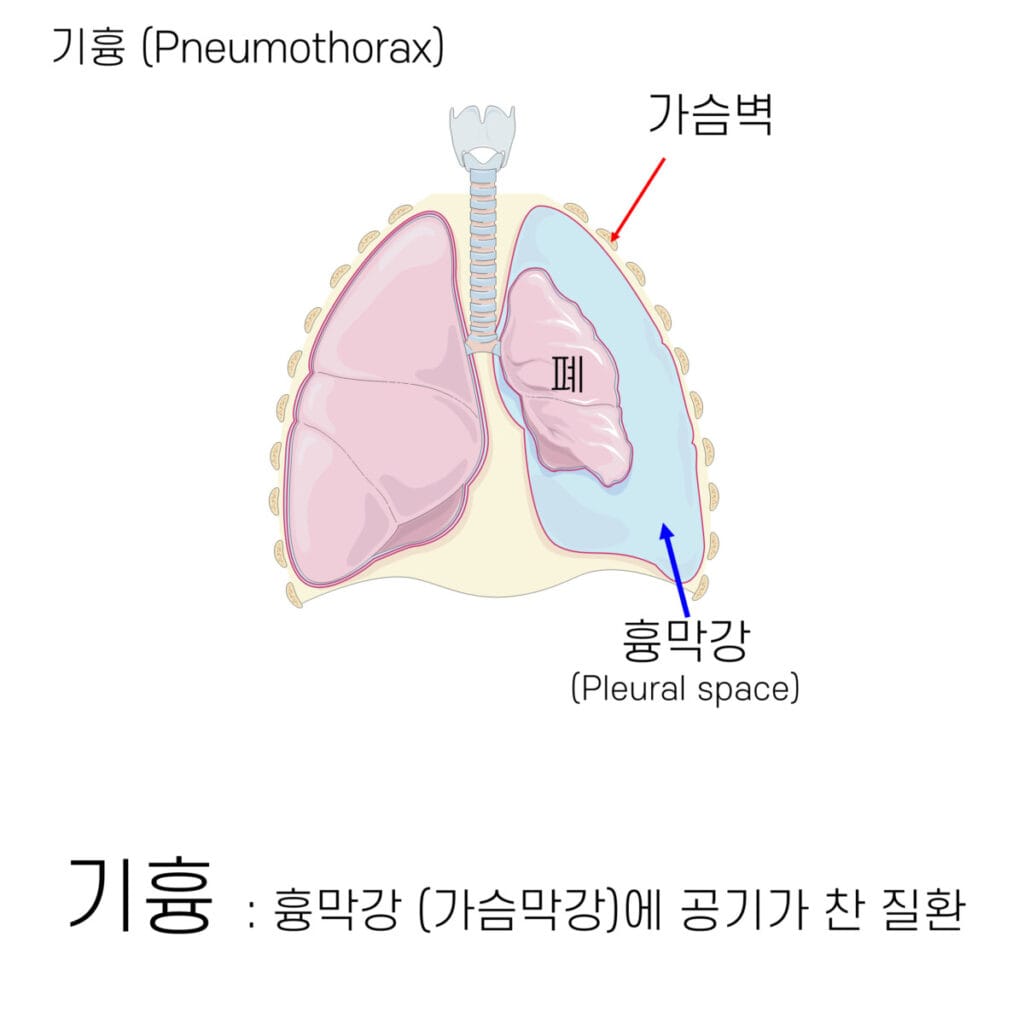

흉막강 (Pleural Space)란?

- 흉막 (Pleura)은 두겹, Parietal Pleura & Visceral Pleura으로 이루어져있습니다. 흉막강은 그 사이 공간을 말합니다.

기흉(Pneumothorax)는 흉강 내에 공기가 비정상적으로 축적되어 폐 허탈을 유발하는 질환입니다.

✅ 기흉은 원인에 따라 자연 기흉, 외상성 기흉, 긴장성 기흉으로 분류되며, 폐의 부피 감소 및 호흡 부전으로 이어질 수 있습니다.